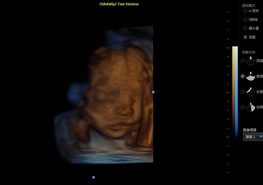

> 3D/4D成像技術(shù)/限7800選配